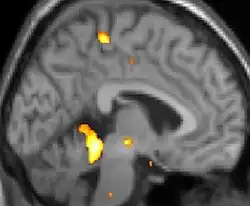

Neuro-imagerie

La tomographie par émission de positons (TEP) montre les zones du cerveau étant activées durant la douleur

Les images par tomographie à émission de positron indiquent les régions du cerveau qui sont activées lors de la douleur, par rapport aux périodes sans douleur. Elles montrent les régions du cerveau qui sont toujours actives durant la douleur en jaune/orange (appelé "matrice-douleur"). La zone au centre (dans les trois vues) est spécifiquement activée uniquement pendant la crise. Les photos sur la ligne du bas (effectuées par VBM) montrent les différences structurelles entre les patients souffrant d'AVF et des personnes saines : seulement une partie de l'hypothalamus est différente[50],[51].